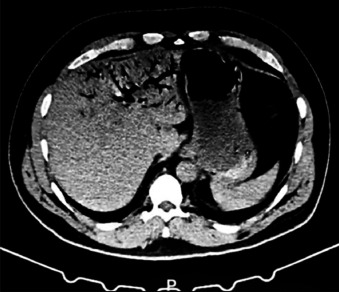

Decompression sickness type II and patent foramen ovale: when a common congenital anomaly becomes a life-threatening risk.